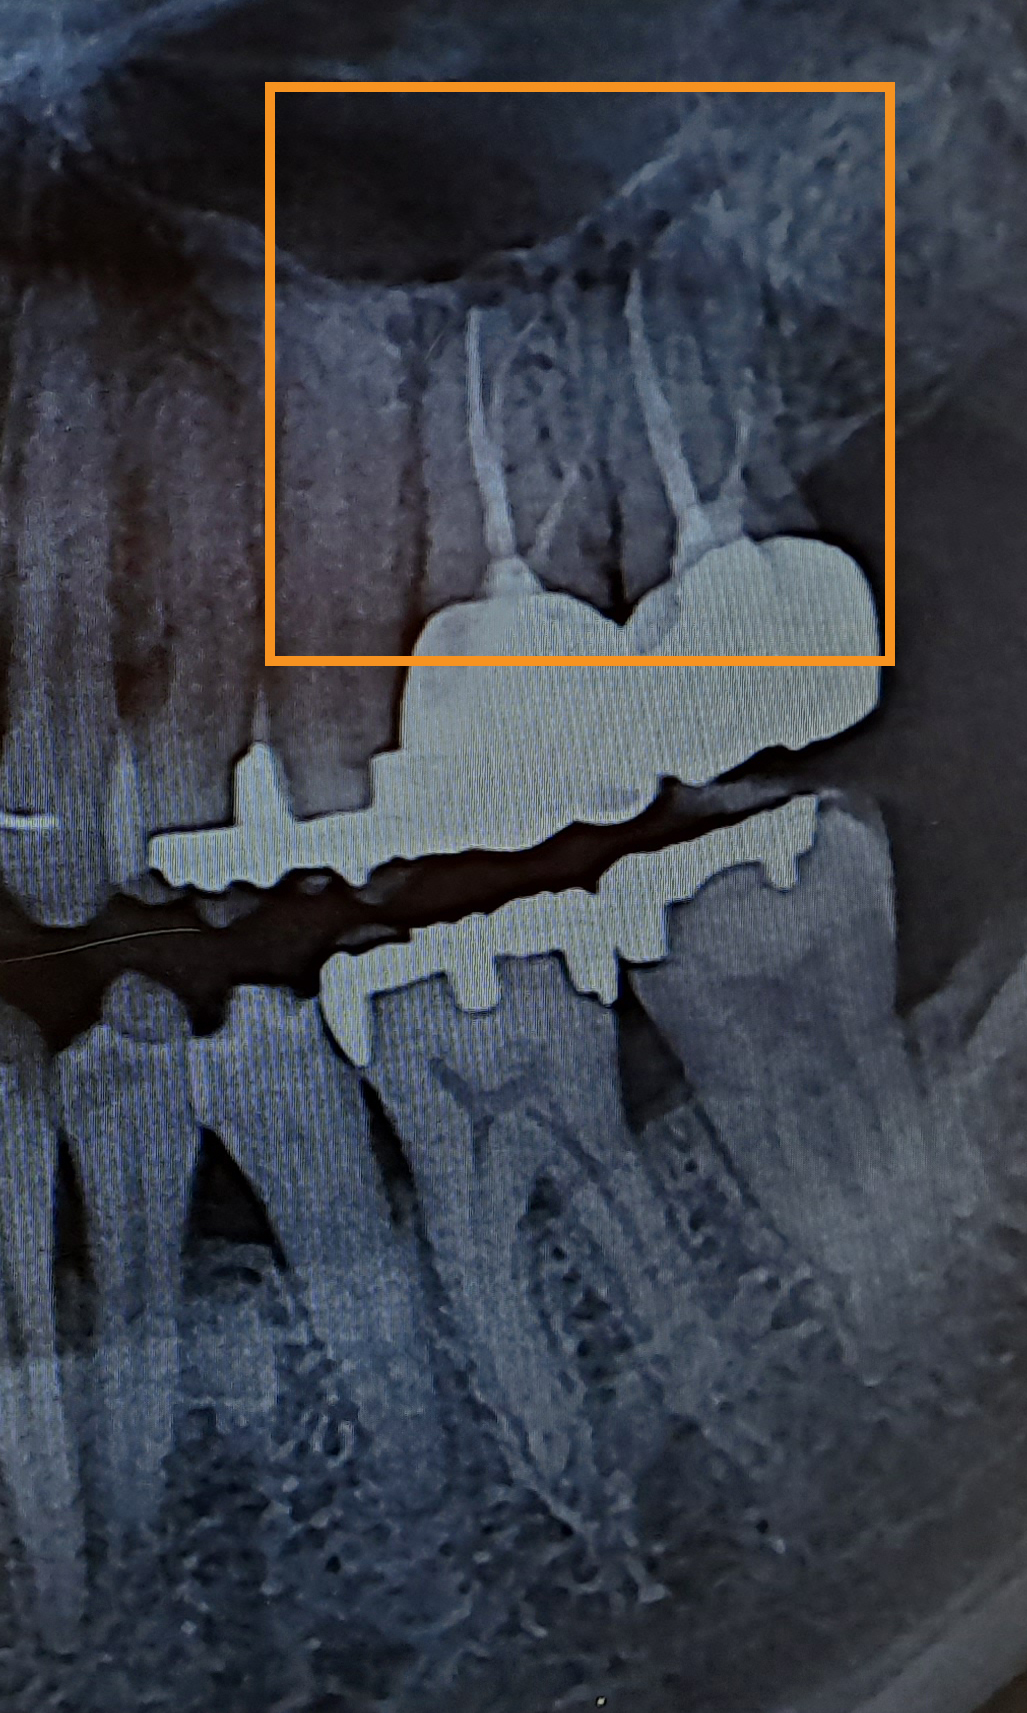

외진곳에 살고있어서 버스타고 30분씩 가야 치과가 겨우 하나 있는 곳에 살고있습니다. 어금니 윗쪽이 아프고 머리가 아파서 치과에 갔는데요. 어느 병원에서는 이정도는 전혀 신경치료나 임플란트같은건 안해도 된다고 하시네요. 그리고 잇몸 염증보다는 이빈후과에 가서 머리쪽과 이빨과 연결된 어딘가가 아플수도 잇으니 이빈후과를 가라고 하시더군요 그래서 오늘 다른 치과에 가서 엑스레이를 찍어봤는데 거기서는 임플란트를 해야 할것 같다고 하시네요. 사진에 있는 검은색 테두리 안쪽 부분과, 주황색 네모 부분 안쪽이 염증으로 보이는 부분인데요. 주황색으로 테두리 친 치과는 이건 염증이 아니라 하시고, 검은색으로 체크해주신 병원은 염증이라고 하시네요. 이미 신경치료를 했던 이빨이기에 더이상 신경치료는 의미가 없고 임플란트를 하라고 하십니다. 비용은 총 100만원 정도구요. (이빨 하나에) 100만원이 작은 돈이 아니라 다른 병원 또 가보고 싶긴한데... 궁금해서 홍차넷에 한번 물어보고 싶습니다. 0